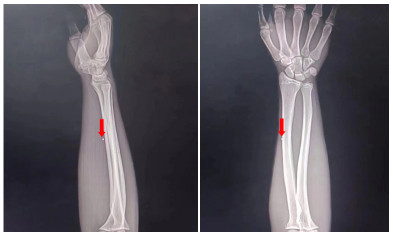

1 资料与方法患者男性,17岁,因“左前臂异物8 h”于2022-05-23 21:25收住急诊抢救室。患者8 h前修车时敲打金属物品,小片金属飞溅至左前臂,伴少量出血,无麻木等不适主诉。后立即于当地医院就诊,X线示异物位置如图 1,当地医院建议转上级医院。上级医院再次行X线检查(图 2),后予以臂丛麻醉下行“左上肢清创+异物取出术”术中未见异物,术后复查X线,左上肢,左肩部以及左侧胸部未见异物,嘱立即转至本院。

| 图 1 外伤后第一次评估异物位置X光检查图像 |